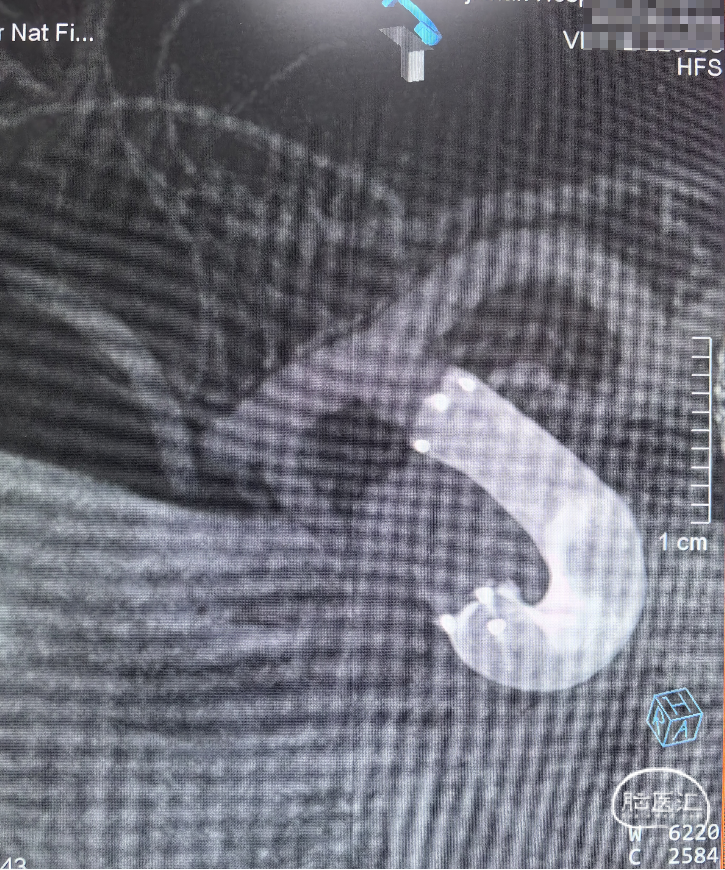

➢ 术前动脉瘤3D

右侧颈内动脉眼动脉段动脉瘤,动脉瘤锥型宽基底,瘤宽6.67mm,瘤高3.68mm,动脉瘤血管远端直径4.86mm,近端直径4.95mm,拟采用密网型号5.0mm*25mm。